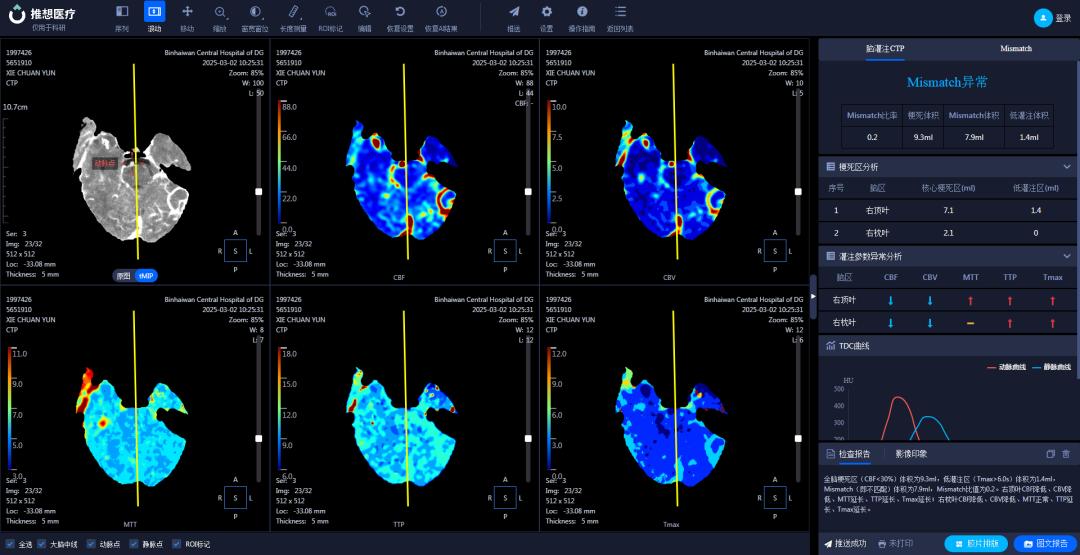

在医学影像科,AI辅助诊断系统宛如一位经验丰富且不知疲倦的医学影像专家,可快速分析肺结节、钼靶检查、骨疾病(骨折)、脑梗塞、脑出血、冠脉CTA(冠状动脉CT血管造影)等影像,提供精准诊断参考,助力医生“一秒读片”。

结合AI技术,256排CT实现去金属伪影、智能心脏重建、一键式卒中流程管理等功能,为心血管疾病和脑卒中患者争取黄金救治时间。